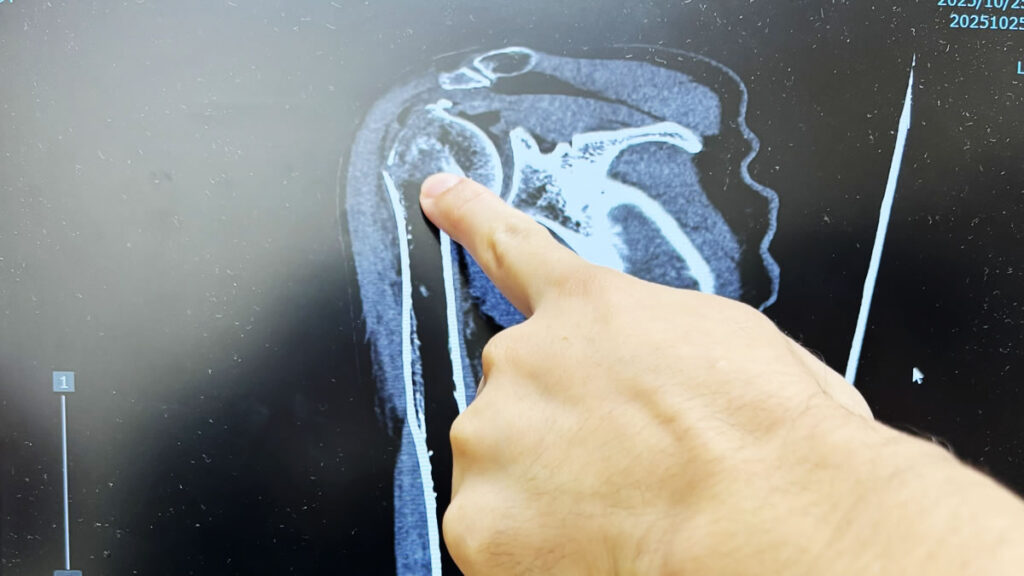

診断の結果、おおぅ上腕の骨が折れているそうな。命に関わる怪我じゃなくて良かったけれど、しばらく生活は不便になりそうだな。。。